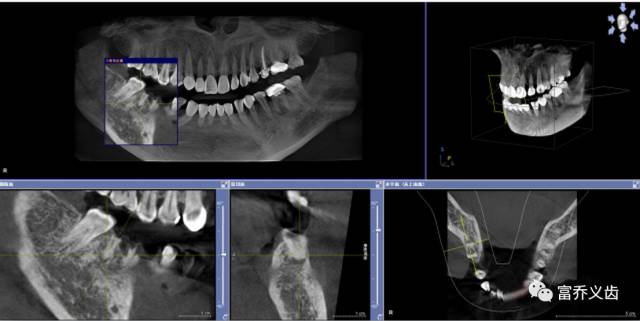

手术后CBCT以及曲面断层片